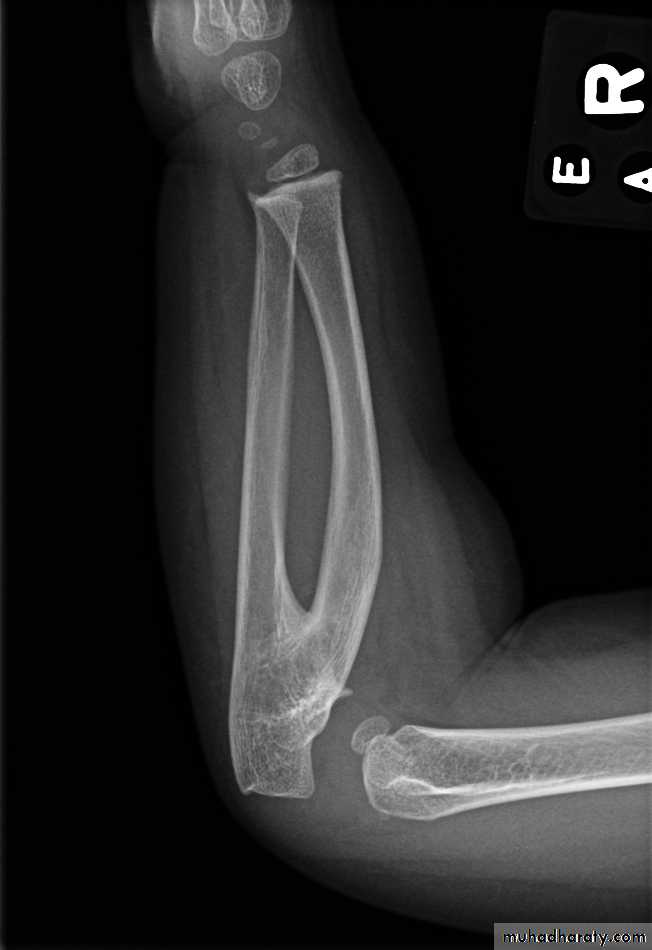

Radioulnar synostosis

Fusion of proximal ulna to the radius, results in sever limitation of forearm pronation and supination. Excision of synostosis is unsuccessful, rotation osteotomy in functional position is the only treatment.CUBITUS VALGUS